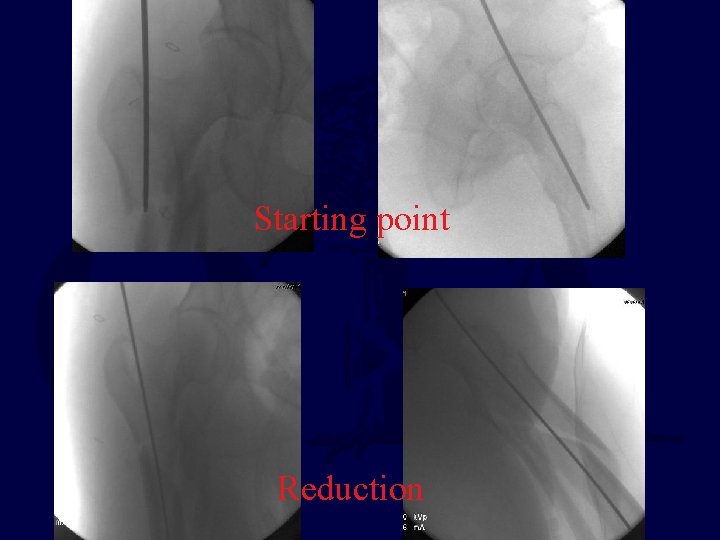

Starting point Reduction